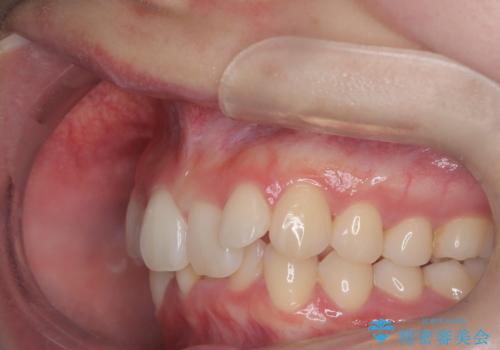

- 患者様は、下顎前歯のガタつきを改善したいとのことで来院されました。診察の結果、スペース不足により前歯が重なっている状態でした。抜歯をせずに並べると前歯が前方に突出してしまうため、下顎の前歯を1本抜歯し、インビザラインで矯正する治療計画を立てました。できる限り追加のアライナーを使用せずに治療を完了できるよう、初回の治療計画を慎重に設計しました。

下顎前歯を1本抜歯し、歯列のスペースを確保。その後、インビザラインを用いて計画通りに歯を移動させ、噛み合わせも整えました。患者様の協力もあり、ゴムかけなどを適切に行い、予定通り1年で治療を完了。追加アライナーを使用することなく、計画通りに治療を終えることができました。患者様からは「思ったより早く終わり、仕上がりにも満足している」と喜びの声をいただきました。